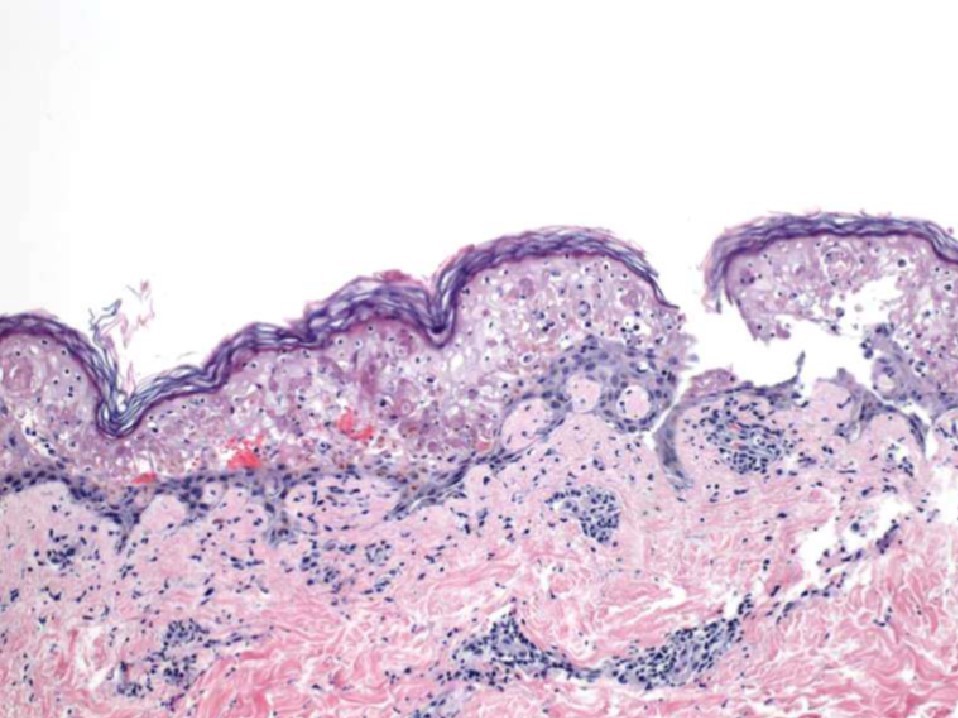

Lupus Erythematosus

Discoid LE (DLE):

Subacute cutaneous LE (SCLE) and systemic LE (SLE):

DIF: